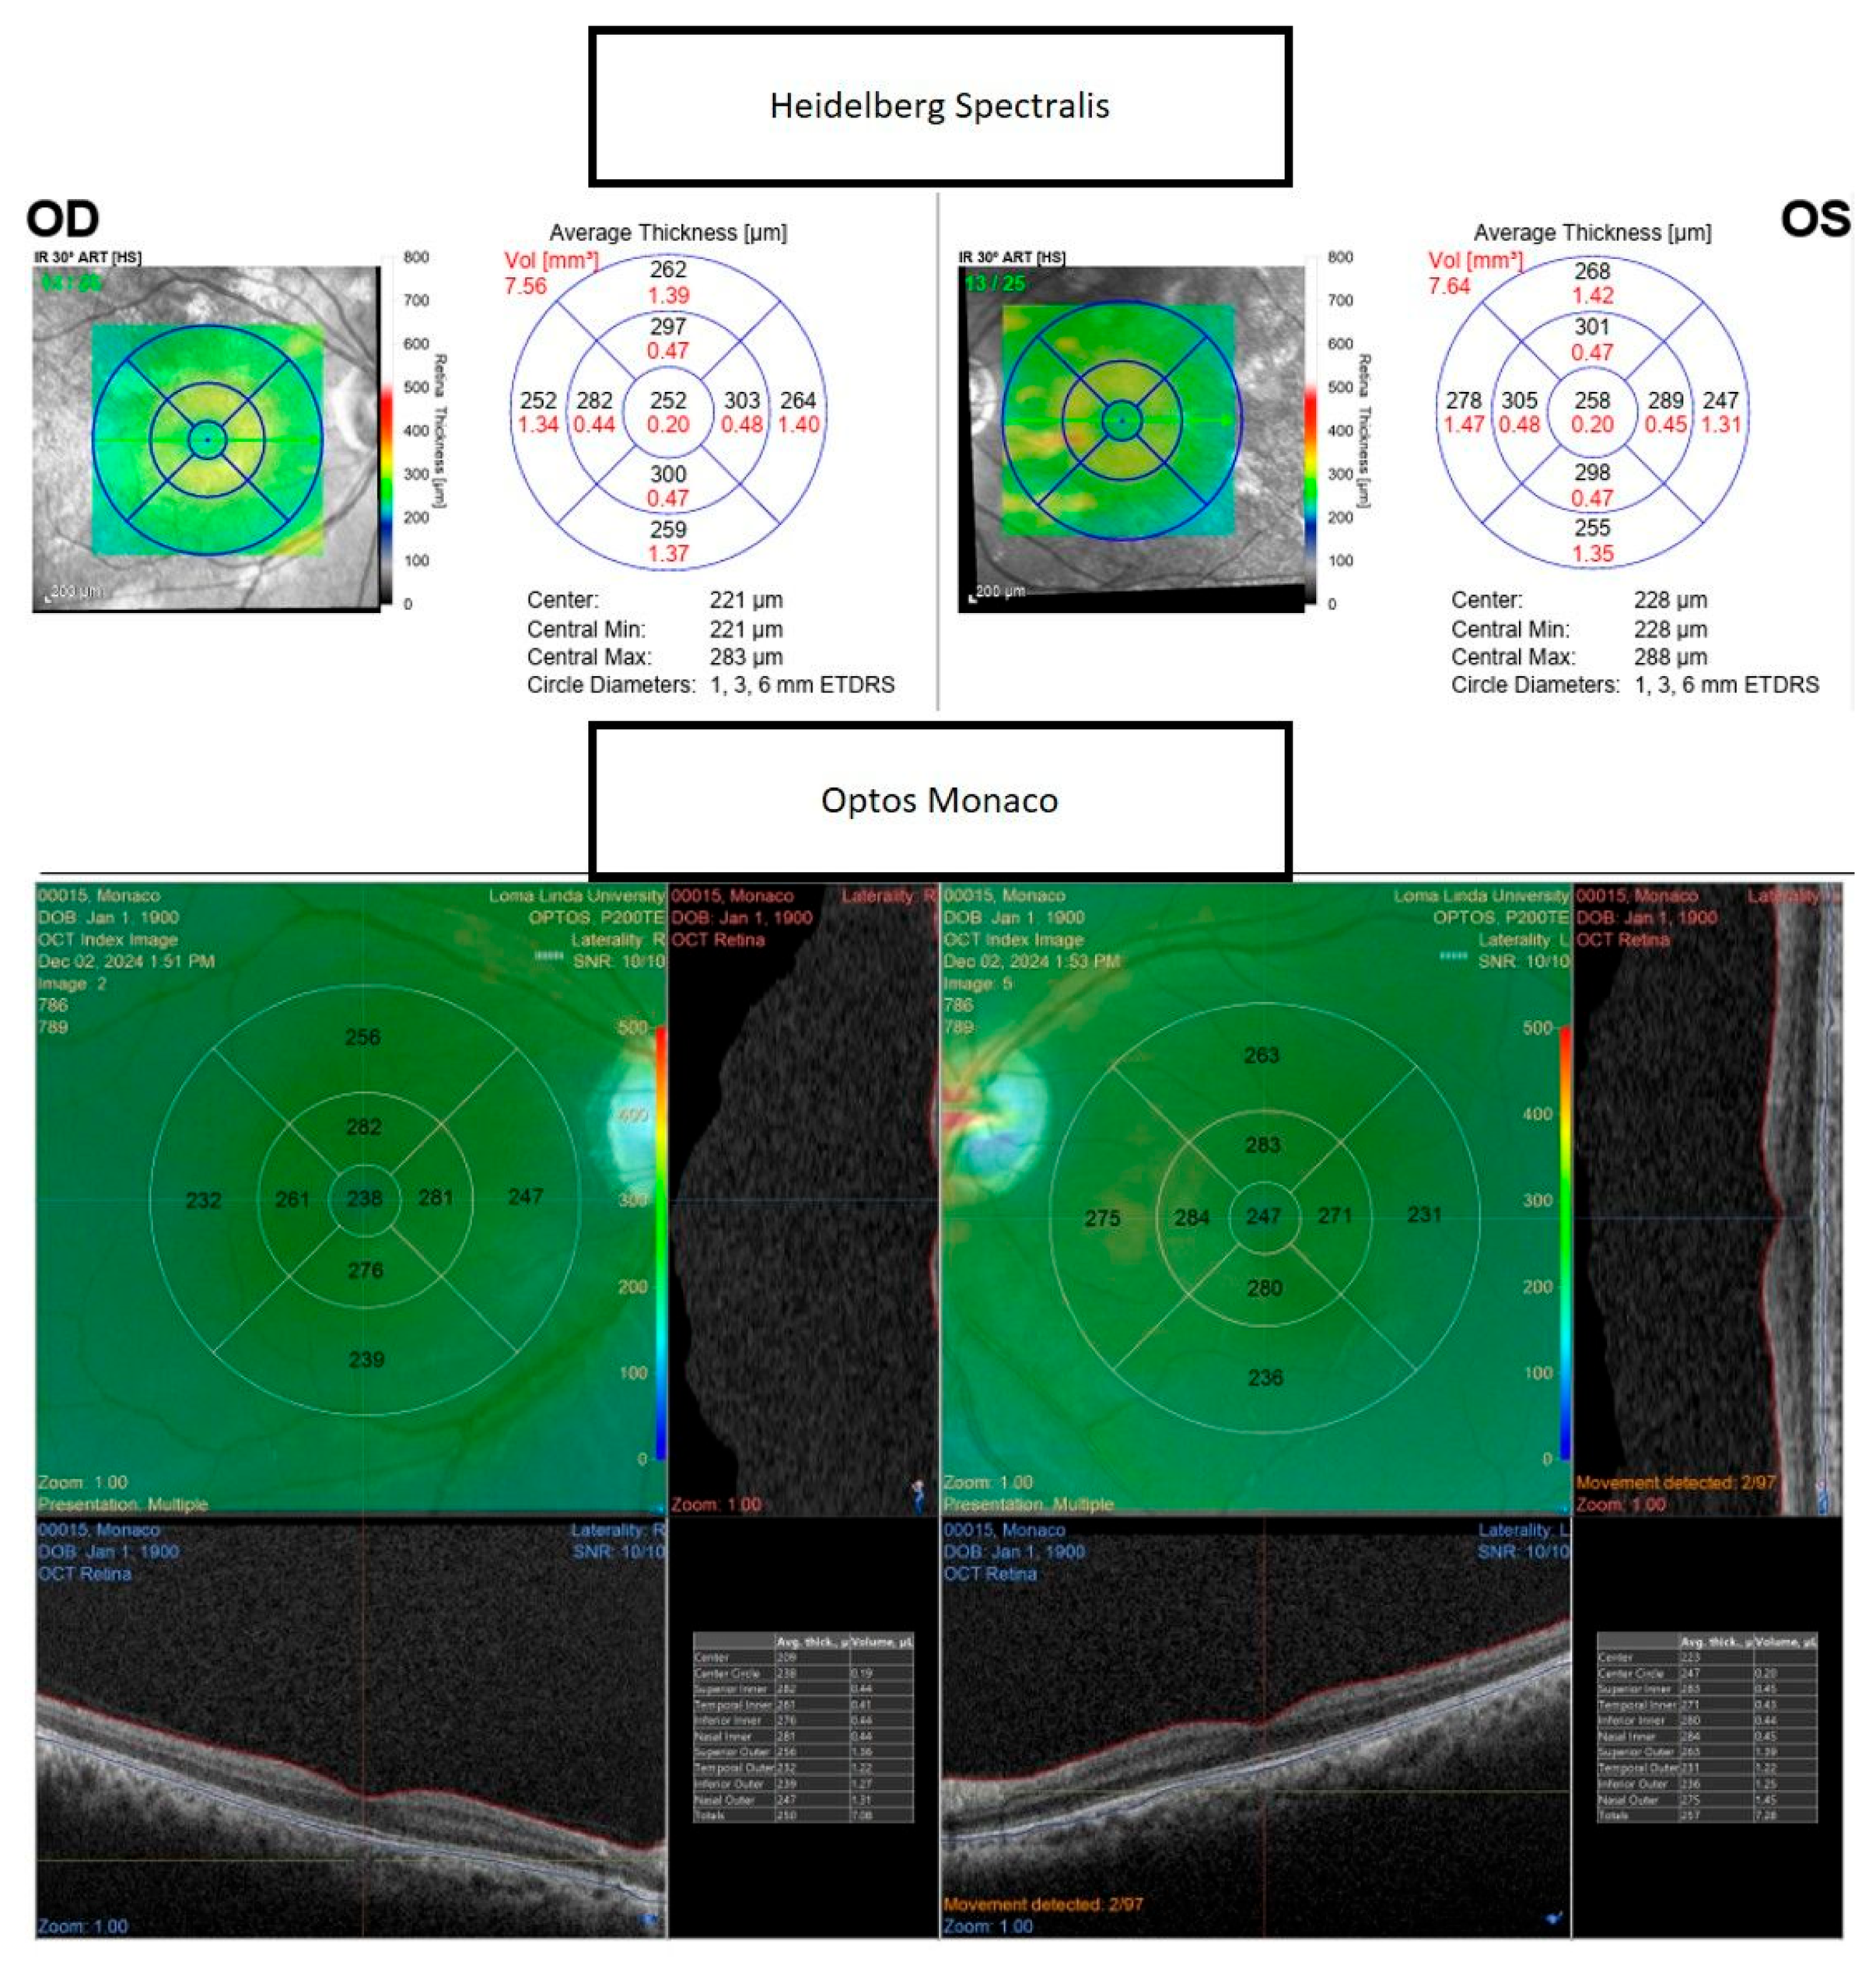

Figure 3. Representative images demonstrate greater retinal thickness values obtained with the Heidelberg Spectralis (upper) compared to the Monaco (lower) Optical Coherence Tomography (OCT) scan of the macula in healthy eyes.

The consistently greater retinal thickness values obtained with the Heidelberg Spectralis (Figure 3) are most plausibly attributable to differences in device-specific segmentation algorithms, scanning protocols, and hardware characteristics. The Heidelberg Spectralis offers an A-scan rate of 85,000 scans per second compared with 70,000 for Optos Monaco, a difference that may improve image stability and reduce motion artifacts [5,7]. The axial resolution of Optos Monaco exceeds that of Heidelberg Spectralis, potentially allowing finer boundary delineation, while its scan depth (2.5 mm vs. 1.9 mm for Spectralis) may influence segmentation by capturing deeper retinal structures [5,7]. These hardware and algorithmic differences underscore the importance of maintaining device consistency in longitudinal studies of macular disease, where subtle variations may alter treatment decisions. Automated segmentation, which delineates retinal boundaries algorithmically, provides greater reproducibility and mitigates certain sources of observer bias inherent in manual caliper measurements. Nonetheless, variations in imaging technology and acquisition protocols between devices—including differences in image quality, resolution, and scanning patterns—may influence the accuracy of automated segmentation. To promote consistency across platforms, automated segmentation algorithms are increasingly validated against multiple spectral-domain OCT devices to confirm their robustness in generating clinically meaningful metrics [8]. Refractive correction and scan quality during image acquisition are also critical, as positive defocus or reduced scan quality can significantly alter retinal nerve fiber layer thickness measurements. Accordingly, this study restricted inclusion to subjects with a refractive error within ±0.50 diopters and best-corrected visual acuity of 20/20 or better to minimize these potential confounders. Future investigations aimed at developing standardized acquisition and analysis protocols are warranted to reduce such biases and enable more reliable comparisons of retinal thickness across devices and studies.